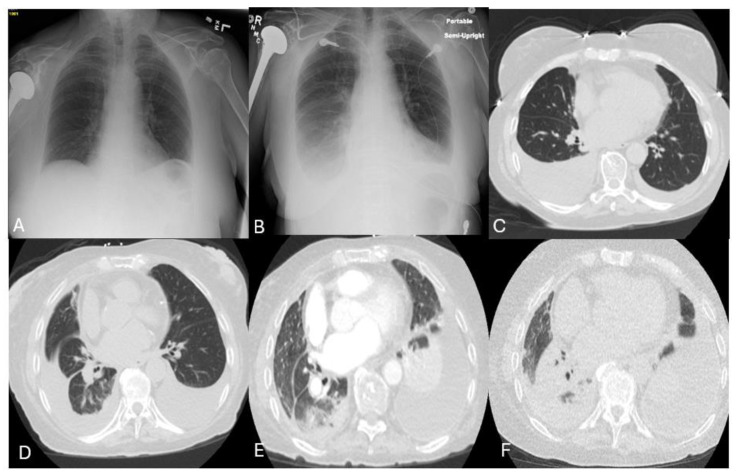

Introduction: Tyrosine kinase inhibitors (TKIs) serve as the backbone in the management of chronic myelogenous leukemia and Philadelphia-positive Acute lymphoblastic Leukemia (Ph+ve ALL). With the growing use of TKIs, there has been an increase in adverse events related to these agents. Hereby, we present elderly women with Ph+ve ALL who developed recurrent pleural effusion, which was managed by switching the TKI and highlighting pleural effusion due to a third-generation TKI Bosutinib, adding to the minimal available literature. Case Description: Our patient is a 79-year-old female with Ph+ve ALL diagnosed in 2015 and started on treatment. She is also on TKI maintenance initially with Imatinib later shifted to second-generation TKIs. She started developing worsening dyspnea related to pulmonary toxicity related to TKI in the form of pleural effusion. Pleural effusion was initially managed with diuretics, later requiring thoracocentesis. Because of persistent pleural effusion, she was changed to multiple TKIs and finally started on Bosutinib. She even developed progressive pleural effusion while on Bosutinib which is managed by thoracocentesis. Conclusions: Through this case report, we would like to highlight refractory recurrent pleural effusion caused by bosutinib adding to the minimal available literature. In addition, we highlight the various treatment options in patients having cross-intolerance to various TKIs, especially pulmonary toxicity, and ponatinib might be a suitable option in such cases.